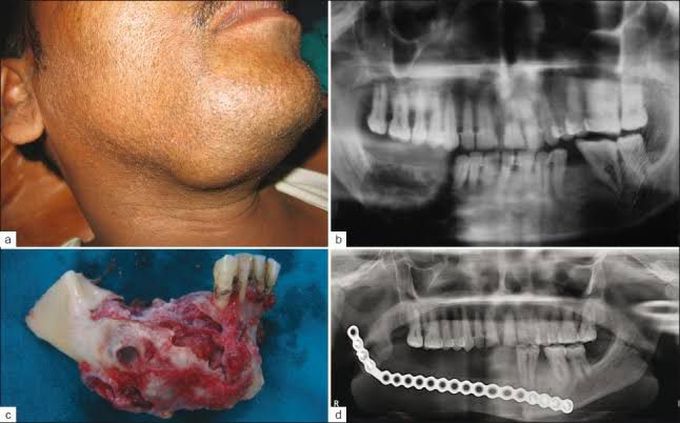

Ameloblastoma is a rare, noncancerous (benign) tumor that develops most often in the jaw near the molars. Ameloblastoma begins in the cells that form the protective enamel lining on your teeth. The most common type of ameloblastoma is aggressive, forming a large tumor and growing into the jawbone.